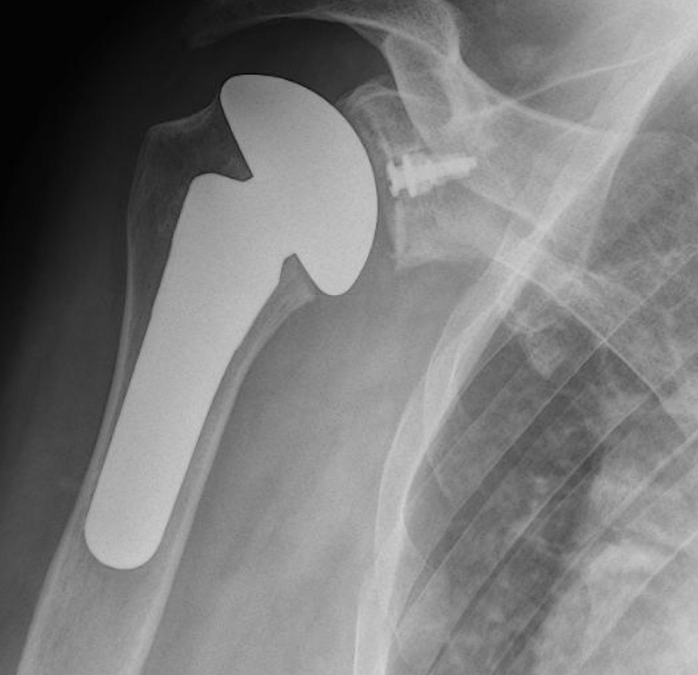

The shoulder is a ball and socket joint. It consists of a round head of the upper arm bone called the humeral head. This ball fits into a socket in the shoulder called the glenoid fossa. A total shoulder replacement removes the damaged round head and socket and replaces them with metal and plastic parts, while maintaining their anatomical position.

A partial shoulder replacement involving the replacement of only the ball or the humeral head with a metal ball and stem. This surgery may be recommended when the humeral head is severely damaged but the socket or the glenoid fossa is normal.

After surgery, you will recover in the hospital for 1 or more days, depending on your individual health conditions and needs. An X-ray will be obtained and your shoulder will be immobilised in a sling. Physiotherapy rehabilitation will begin almost immediately following the surgical procedure. The initial goals of treatment are to reduce swelling and pain, while restoring passive motion. Subsequently, the treatment goals shift to active motion, strengthening the shoulder and increased functionality of the affected arm. A tailored, well planned rehabilitation program is essential for the success of a shoulder replacement in the hospital and while recovering at home.

Choosing the right hand therapist starts with them being able to read your X-rays and then fabricate the right brace for you. The therapists at Action Rehab are experienced in assessing and reading X-rays.